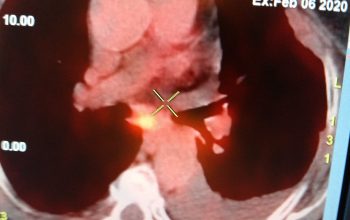

Παραδείγματα πότε μπορεί να βοηθήσει η εξέταση (ΕBUS) στη διάγνωση

Εικόνες από τη διαδίκασια της ταχείας βιοψίας μέσα στην αίθουσα ενδοσκόπησης